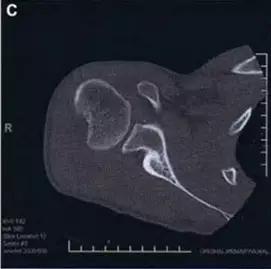

9. Essex-Lopresti 骨折

是桡骨头骨折伴有下尺桡关节脱位,导致骨间膜损伤,桡骨短缩。此种损伤,桡骨头骨折的诊断往往是明确的,容易忽视的是下尺桡关节脱位,特别是早期,下尺桡关节的症状不明显,X 线表示也不明显。

Essex-Lopresti 损伤。前后位(A)和侧位(B)示桡骨头关节内骨折(白色实线箭头);(C~E)伤后 1 个月复诊,患者诉腕关节疼痛,X 线(C,D)发现下尺桡关节脱位,(E)CT 进一步证实损伤的存在 (来源:Radiol Clin North Am. 2015 Jul;53(4):717-36)